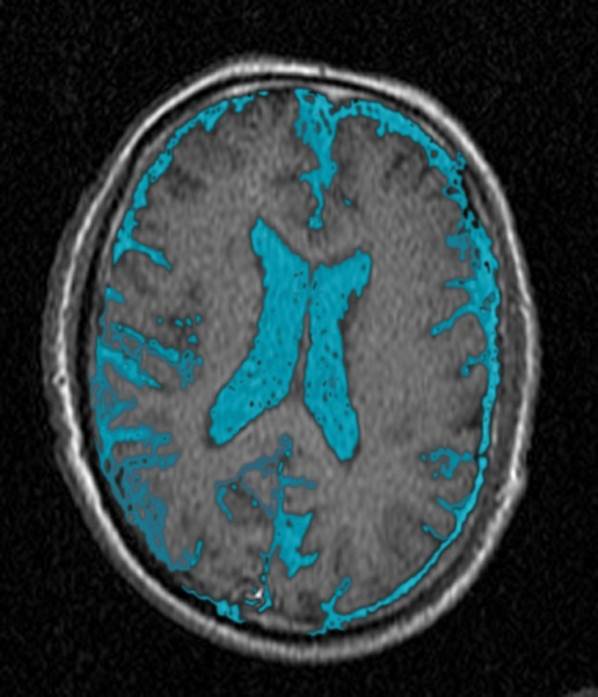

CT: Brain Atrophy

10 Years-Normal Gyri             65 Years-Enlarged Gyri